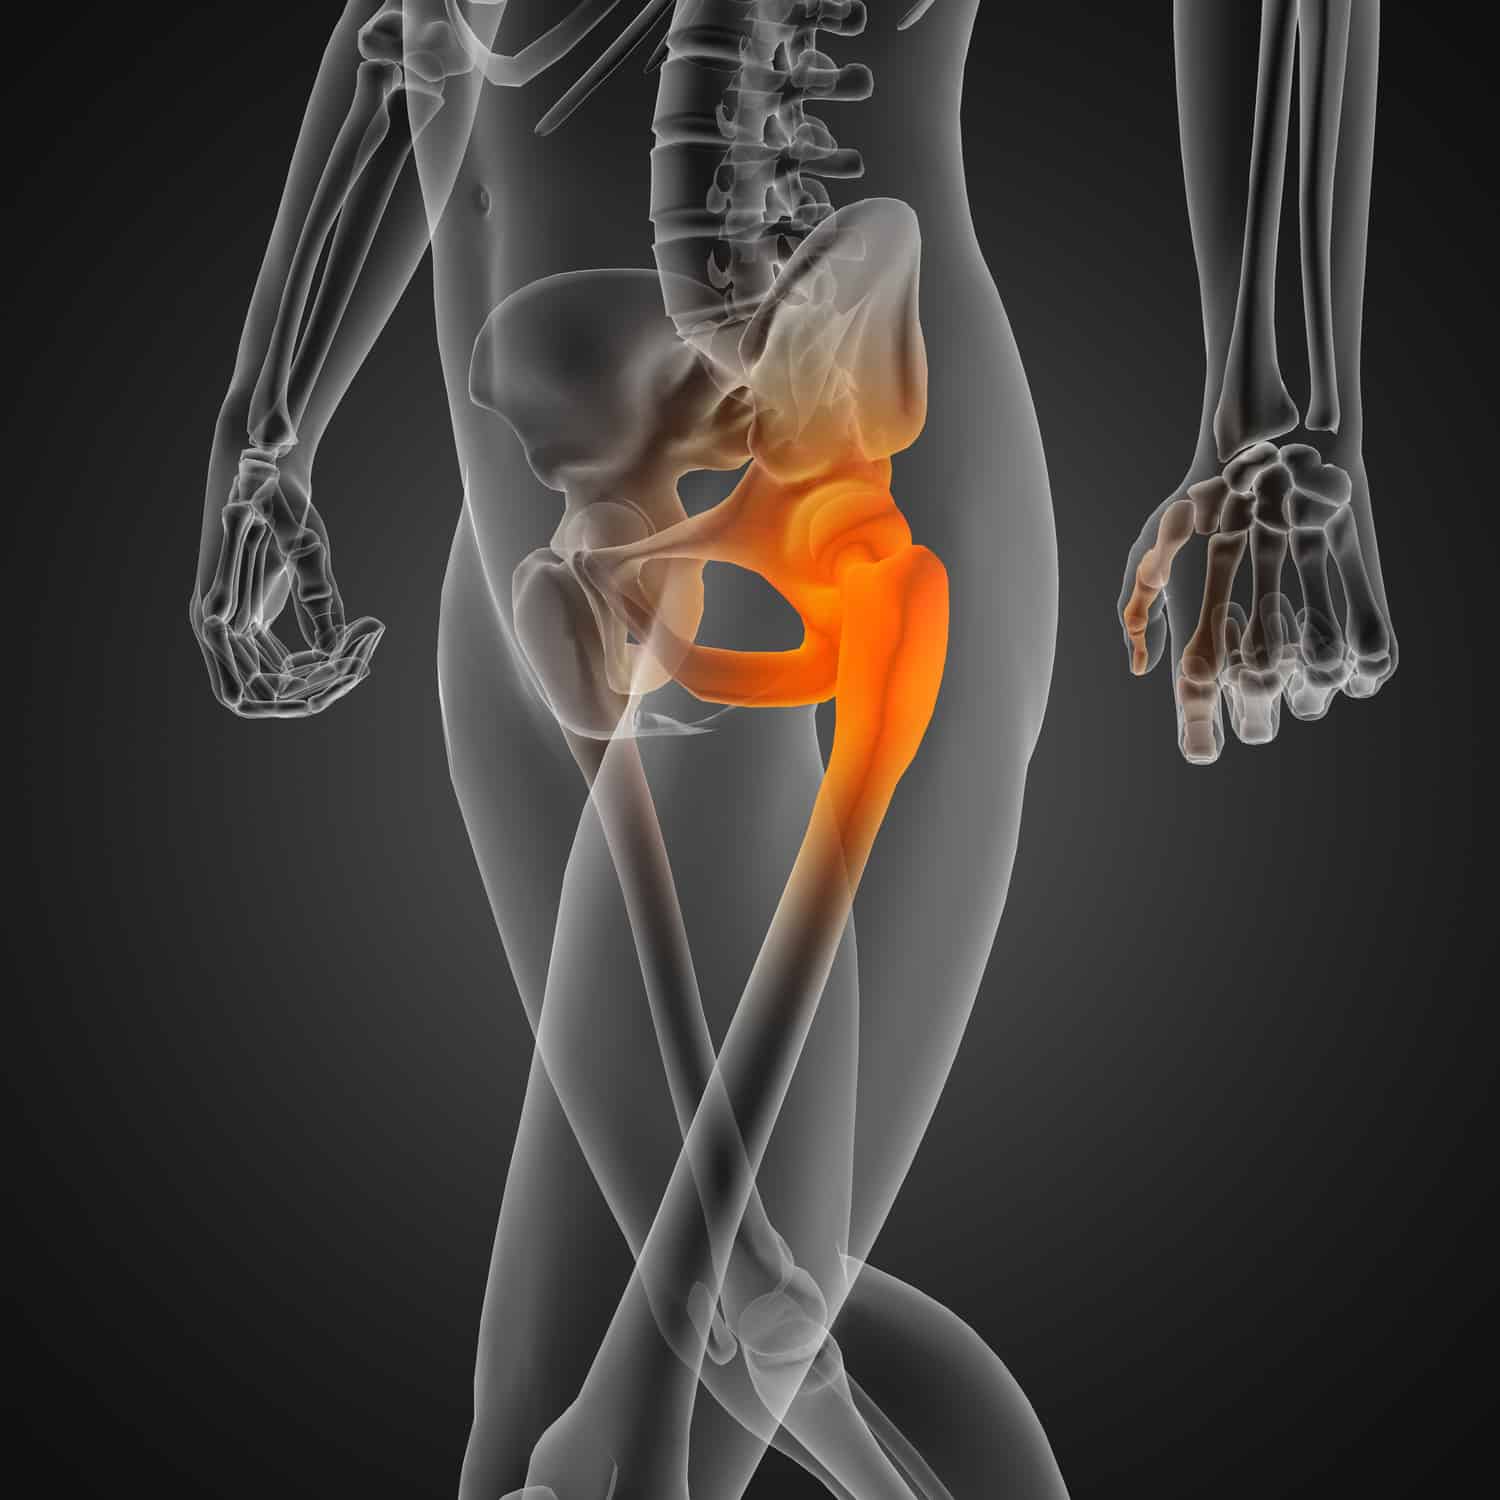

Hip Surgery

Hip